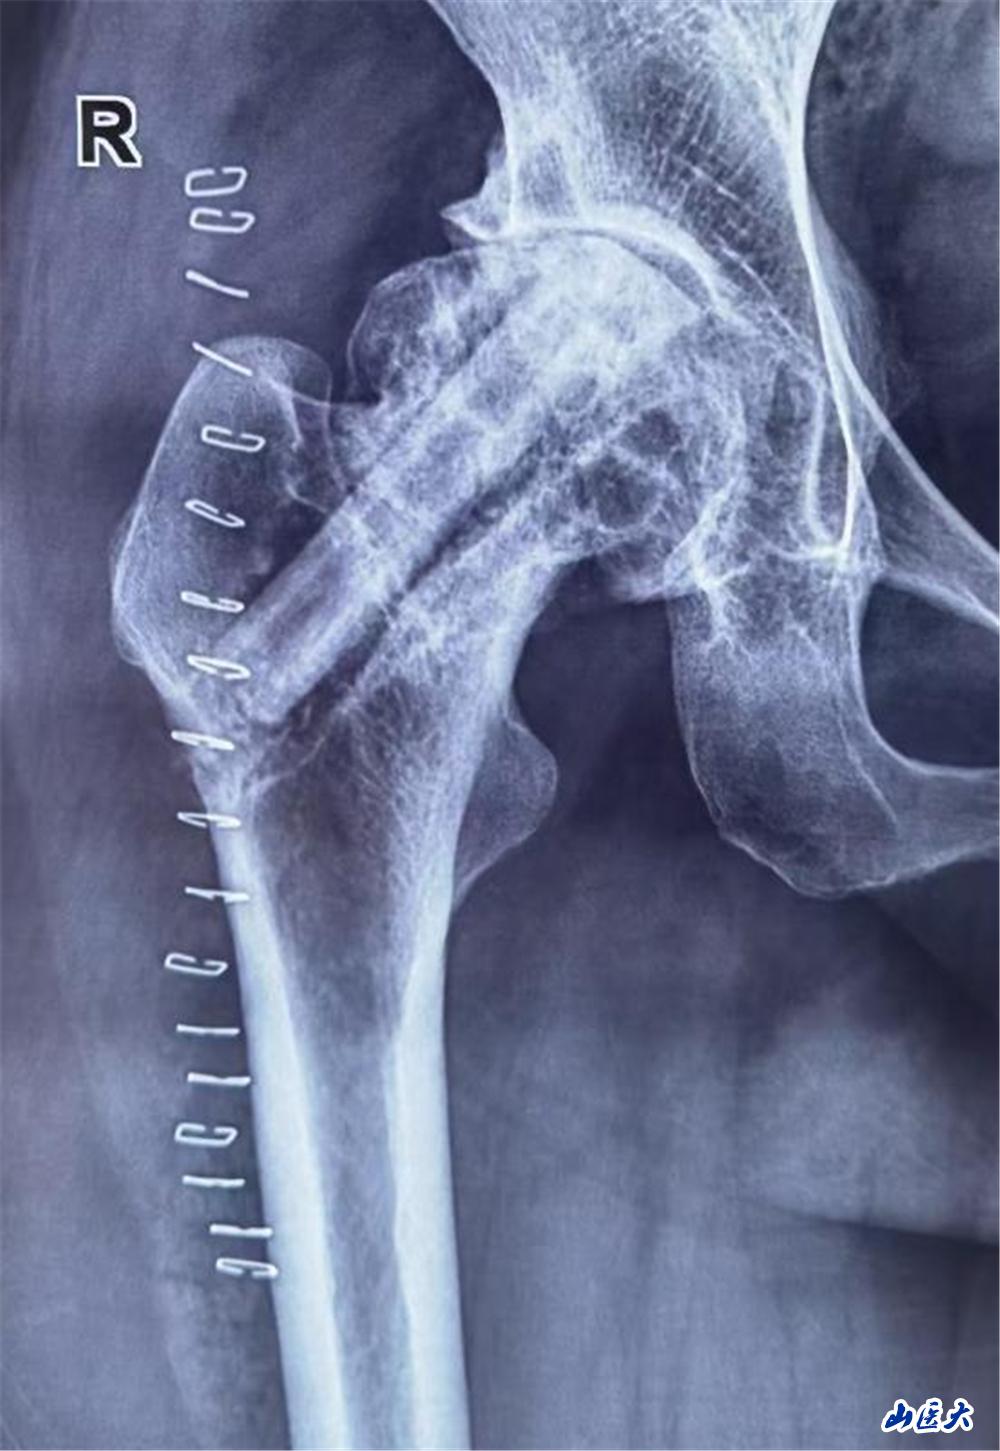

陈大姐饱受股骨头坏死折磨3年,近一个月疼痛加重,行走困难。面对患者强烈的保髋愿望,医疗团队术前通过影像学检查及血管评估,精准分析患者股骨头坏死范围及血供情况,为其量身定制了“带血管蒂的腓骨瓣移植”手术方案。这一术式能重建股骨头血运,延缓甚至避免关节置换,但对医生的显微外科技术要求极高。

手术当日面临巨大挑战,医疗团队需在患者腓骨处截取长约6cm的带血管骨瓣,并在显微镜下将细如发丝的旋髂外侧动脉与股骨头供血血管吻合。5个半小时的奋战,每一步都考验着团队的默契与技艺。